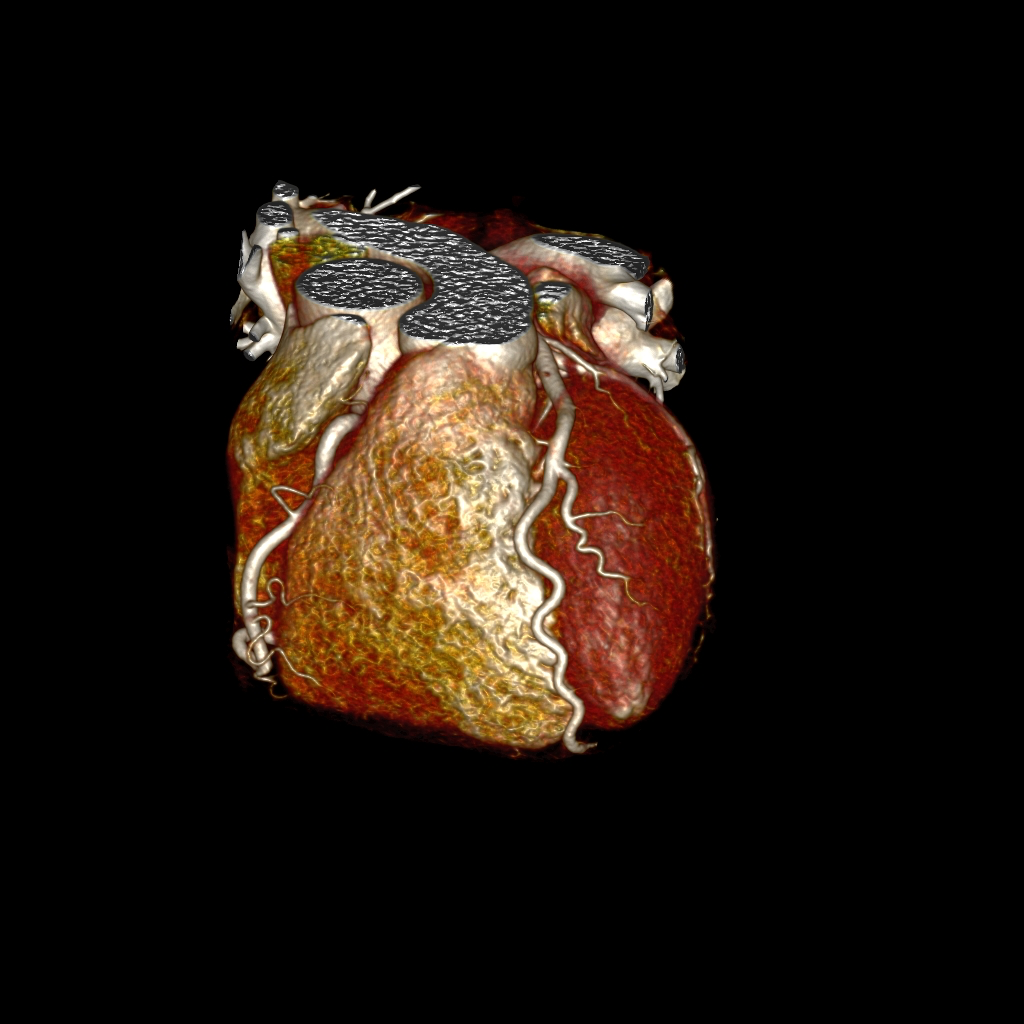

- Für die Darstellung von Gefäßen, Aneurysmen (insb. der Aorta) oder Verengungen/Verschlüssen

- Zur Untersuchung der Herzkranzarterien (Kardio-CT )